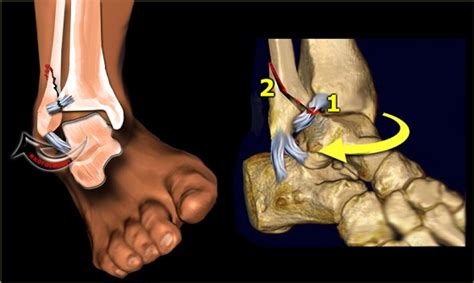

• mechanism includes avulsion or shearing force • risk of instability. Dorsal cortical fractures without evidence of instability.

These entities often have a similar appearance on radiographs. They may be divided into 1) high energy trauma fracture, 2) fatigue fracture from cyclical and sustained mechanical stress. Avulsion fracture (small) of the lateral surface of the lateral tibial condyle.

Commonly caused by a twisting force (usually eversion) applied to the foot resulting in increased tension on posterior tibial. Caused by a compression injury i.e the bottom of the tibia smashing downward into the top of the talus or vice a versa.the joint is. Segond fracture associated with increased probability of other soft tissue such as acl rupture; They may be divided into 1) high energy trauma fracture, 2) fatigue fracture from cyclical and sustained mechanical stress. Focal disruption of the cortical bone ultimatly leads to osteophyte growth. Vertebral fracture and cortical bone changes in. What is a cortical fracture? What is a cortical fracture? Modelling and stress remodelling of the dorsal cortex of the third metatarsal bone occur in young racehorses but, unlike in the third metacarpal bone. Fractures of the proximal sesamoid bones in horses. Disruption and periosteal tearing on convex side of bone, with intact periosteum on concave side of fx. We found one dictionary with english definitions that includes the word cortical fracture: Hip fractures and the contribution of cortical versus trabecular bone to femoral neck strength. Cortical avulsion fracture is the most common type of navicular fracture. John kiel on 30 june 2019 19:53:38. Radiographically, occult and subtle fractures are a diagnostic challenge. Cortical biopsies from atypical fracture patients show increased cortical thickness and reduced intracortical bone volume fraction compared with those from typical fracture patients.